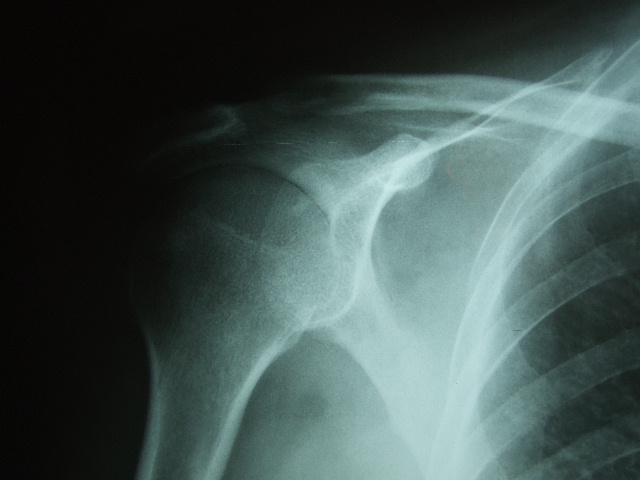

Fractura impactada de húmero .

Fractura de húmero.

Fractura compleja de húmero.